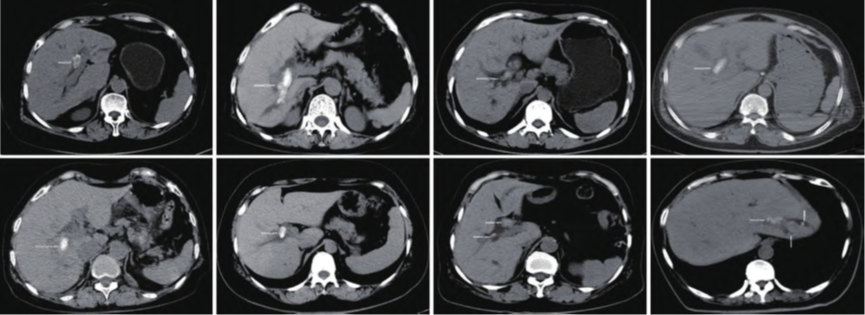

640.png

8Àý¸Îµ¨¹Ü½áʯ»¼ÕßÒºµçËéʯÖÎÁƵÄCTÌåÏÖ£¨°×É«¼ýÍ·ËùָΪ½áʯ£©